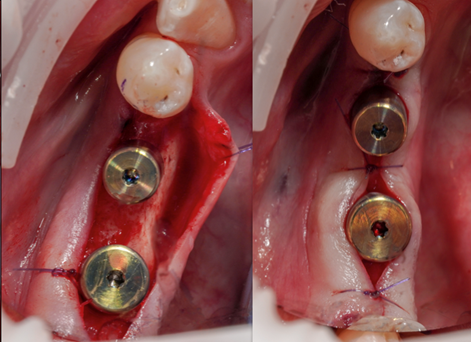

• Živý zákrok na pacientovi

• 13:00 – 14:30 LIVE zákrok soloimplantace na pacientovi.